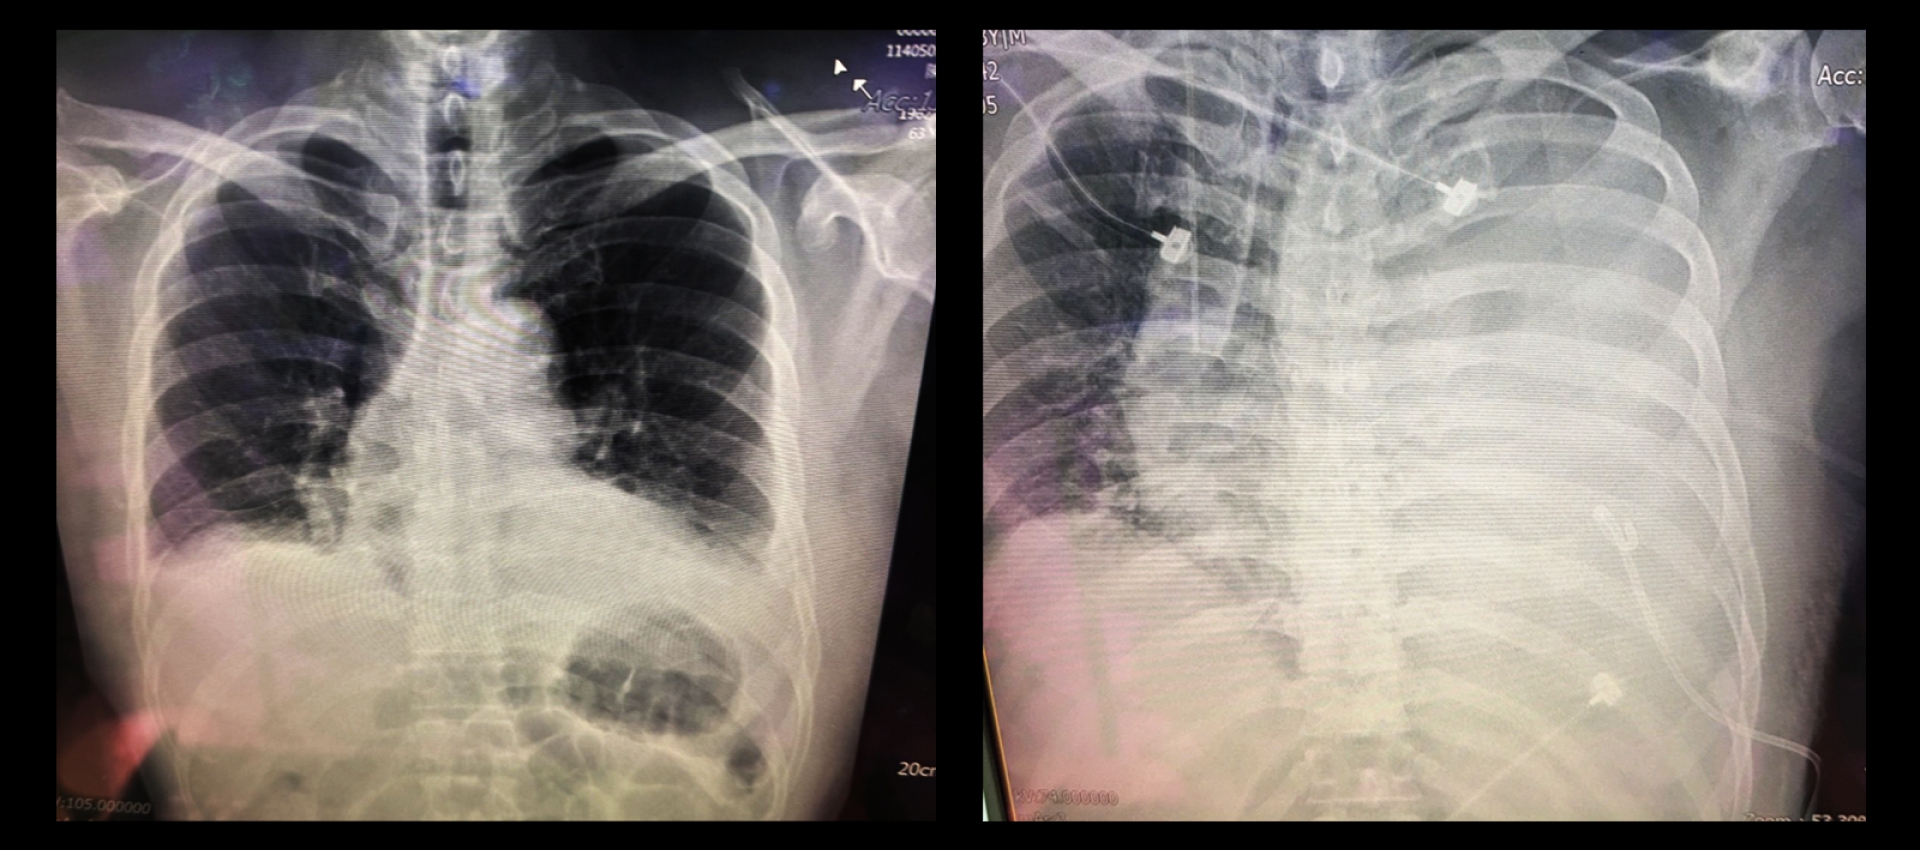

Cardinal Tien Hospital Case

With the availability of OCEAN’s rib fixation plates, patients can experience significantly reduced complications.